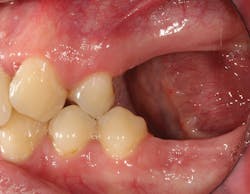

• site development to increase hard and soft tissue for pontic sites in fixed bridge prosthetics (figures 9–14);• correcting bone defects impinging upon anatomical structures after tooth extraction, such as oroantral communication (figure 18); and